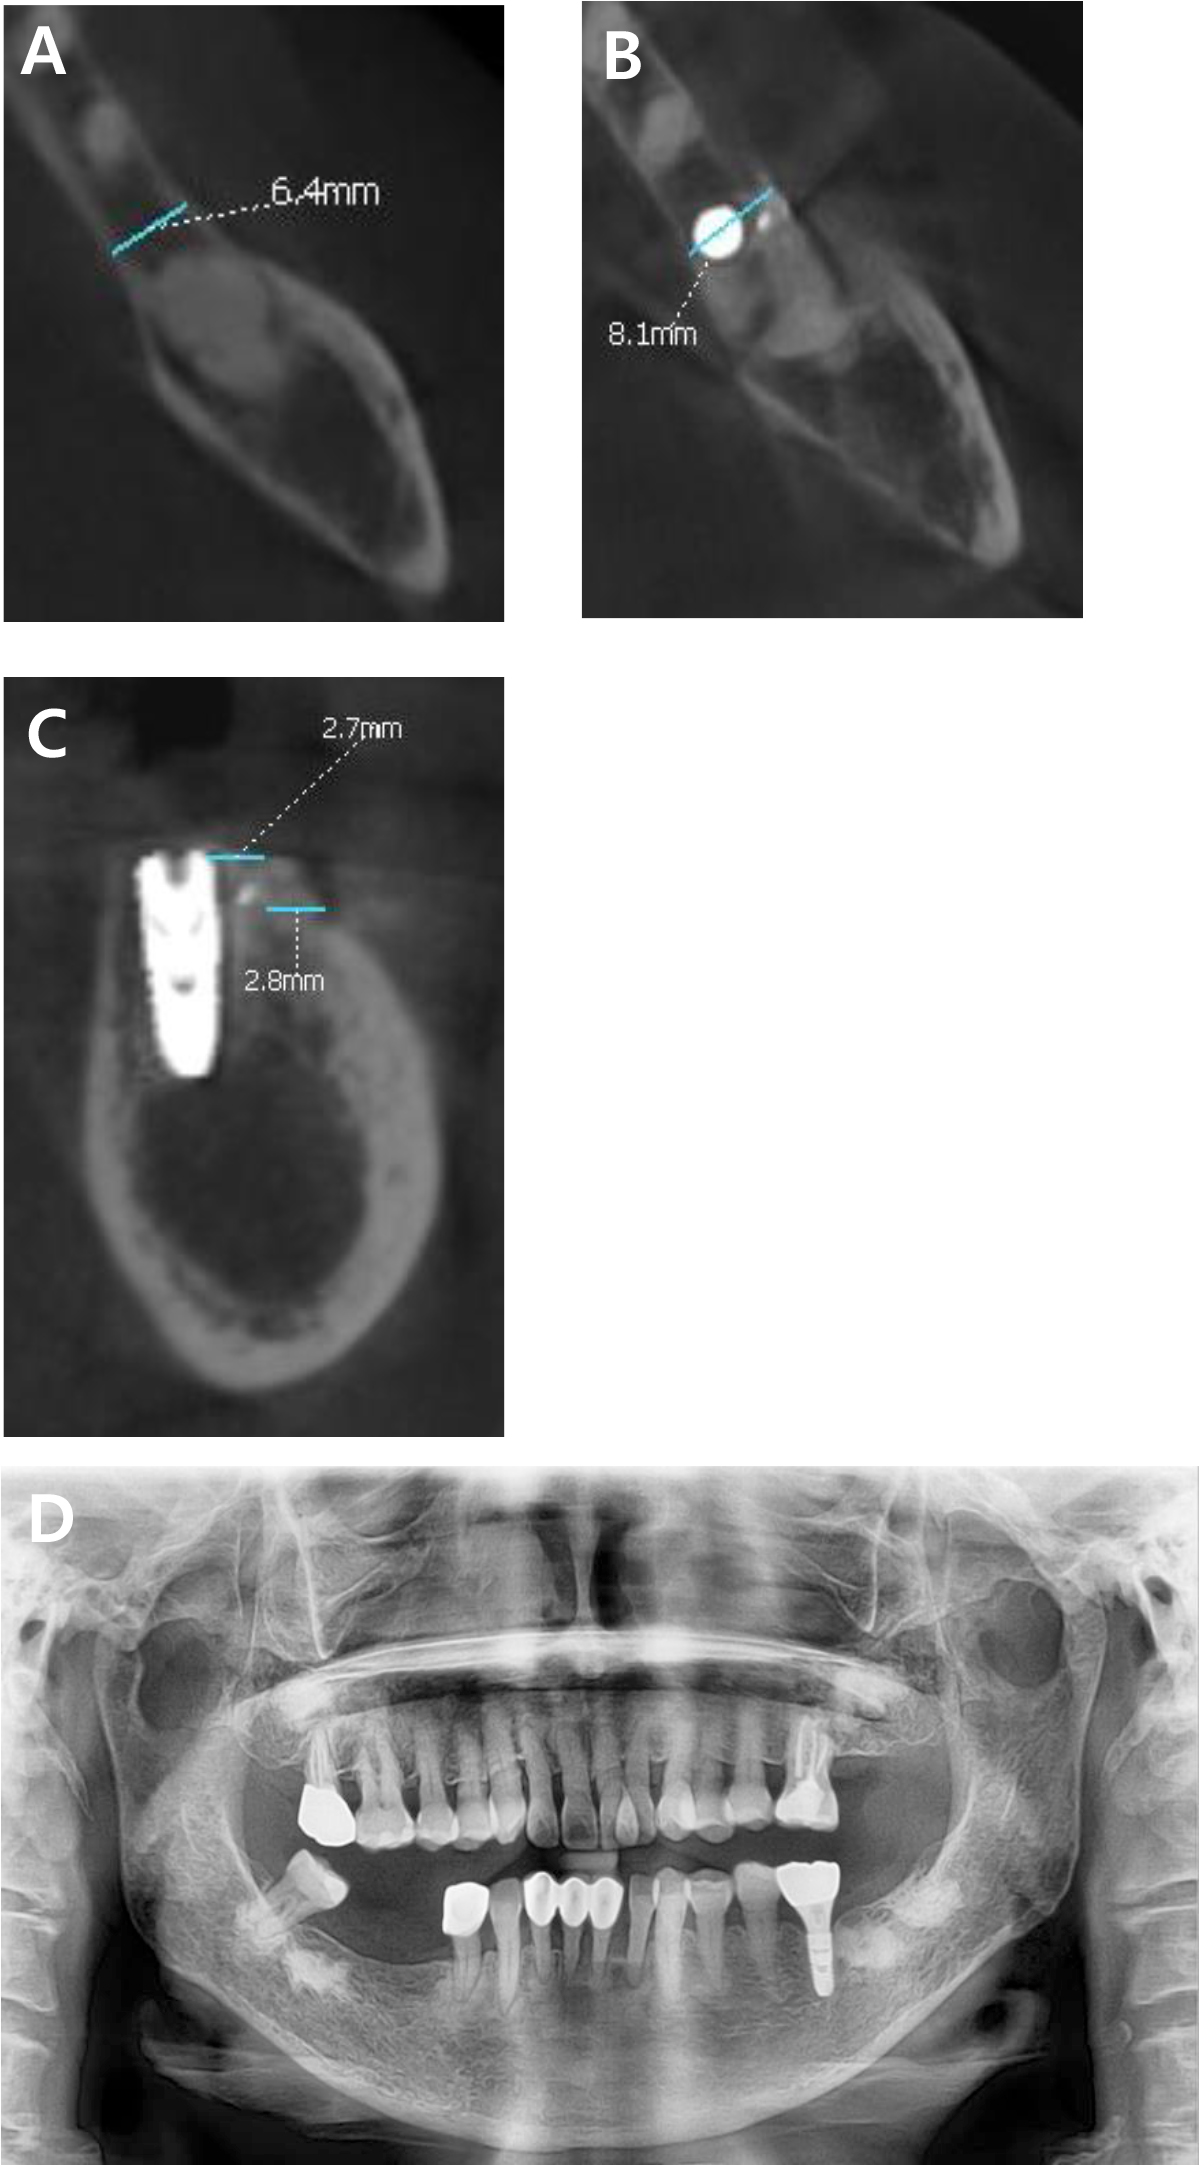

Preoperative cone-beam computed tomography (CBCT) revealed horizontal alveolar bone deficiency due to long-term edentulism. To ensure long-term implant success, approximately 1–2 mm of HRA was considered necessary. Accordingly, simultaneous placement of a 4 mm diameter implant was planned, along with HRA using ADM loaded with rhBMP-2.

CBCT analysis performed 5 months postoperatively confirmed a horizontal bone gain of approximately 1.7 mm. Newly formed bone with homogeneous density and continuity was observed around the implant (Fig. 6). Throughout the 10-month functional loading period, no signs of inflammation, bone resorption, or other complications were observed in the surrounding hard or soft tissues. The implant remained functionally stable.

Fig. 6

(A) Preoperative cone-beam computed tomography (CBCT) scan showing the alveolar bone width at the level corresponding to the fixation screw position in the postoperative scan. (B) CBCT scan 5 months postoperatively showing a horizontal bone gain of 1.7 mm. (C) Sagittal CBCT view showing buccal cortical bone thickness at the level of the bone crest and 2 mm below the crest after surgery. (D) Panoramic radiograph after functional loading.